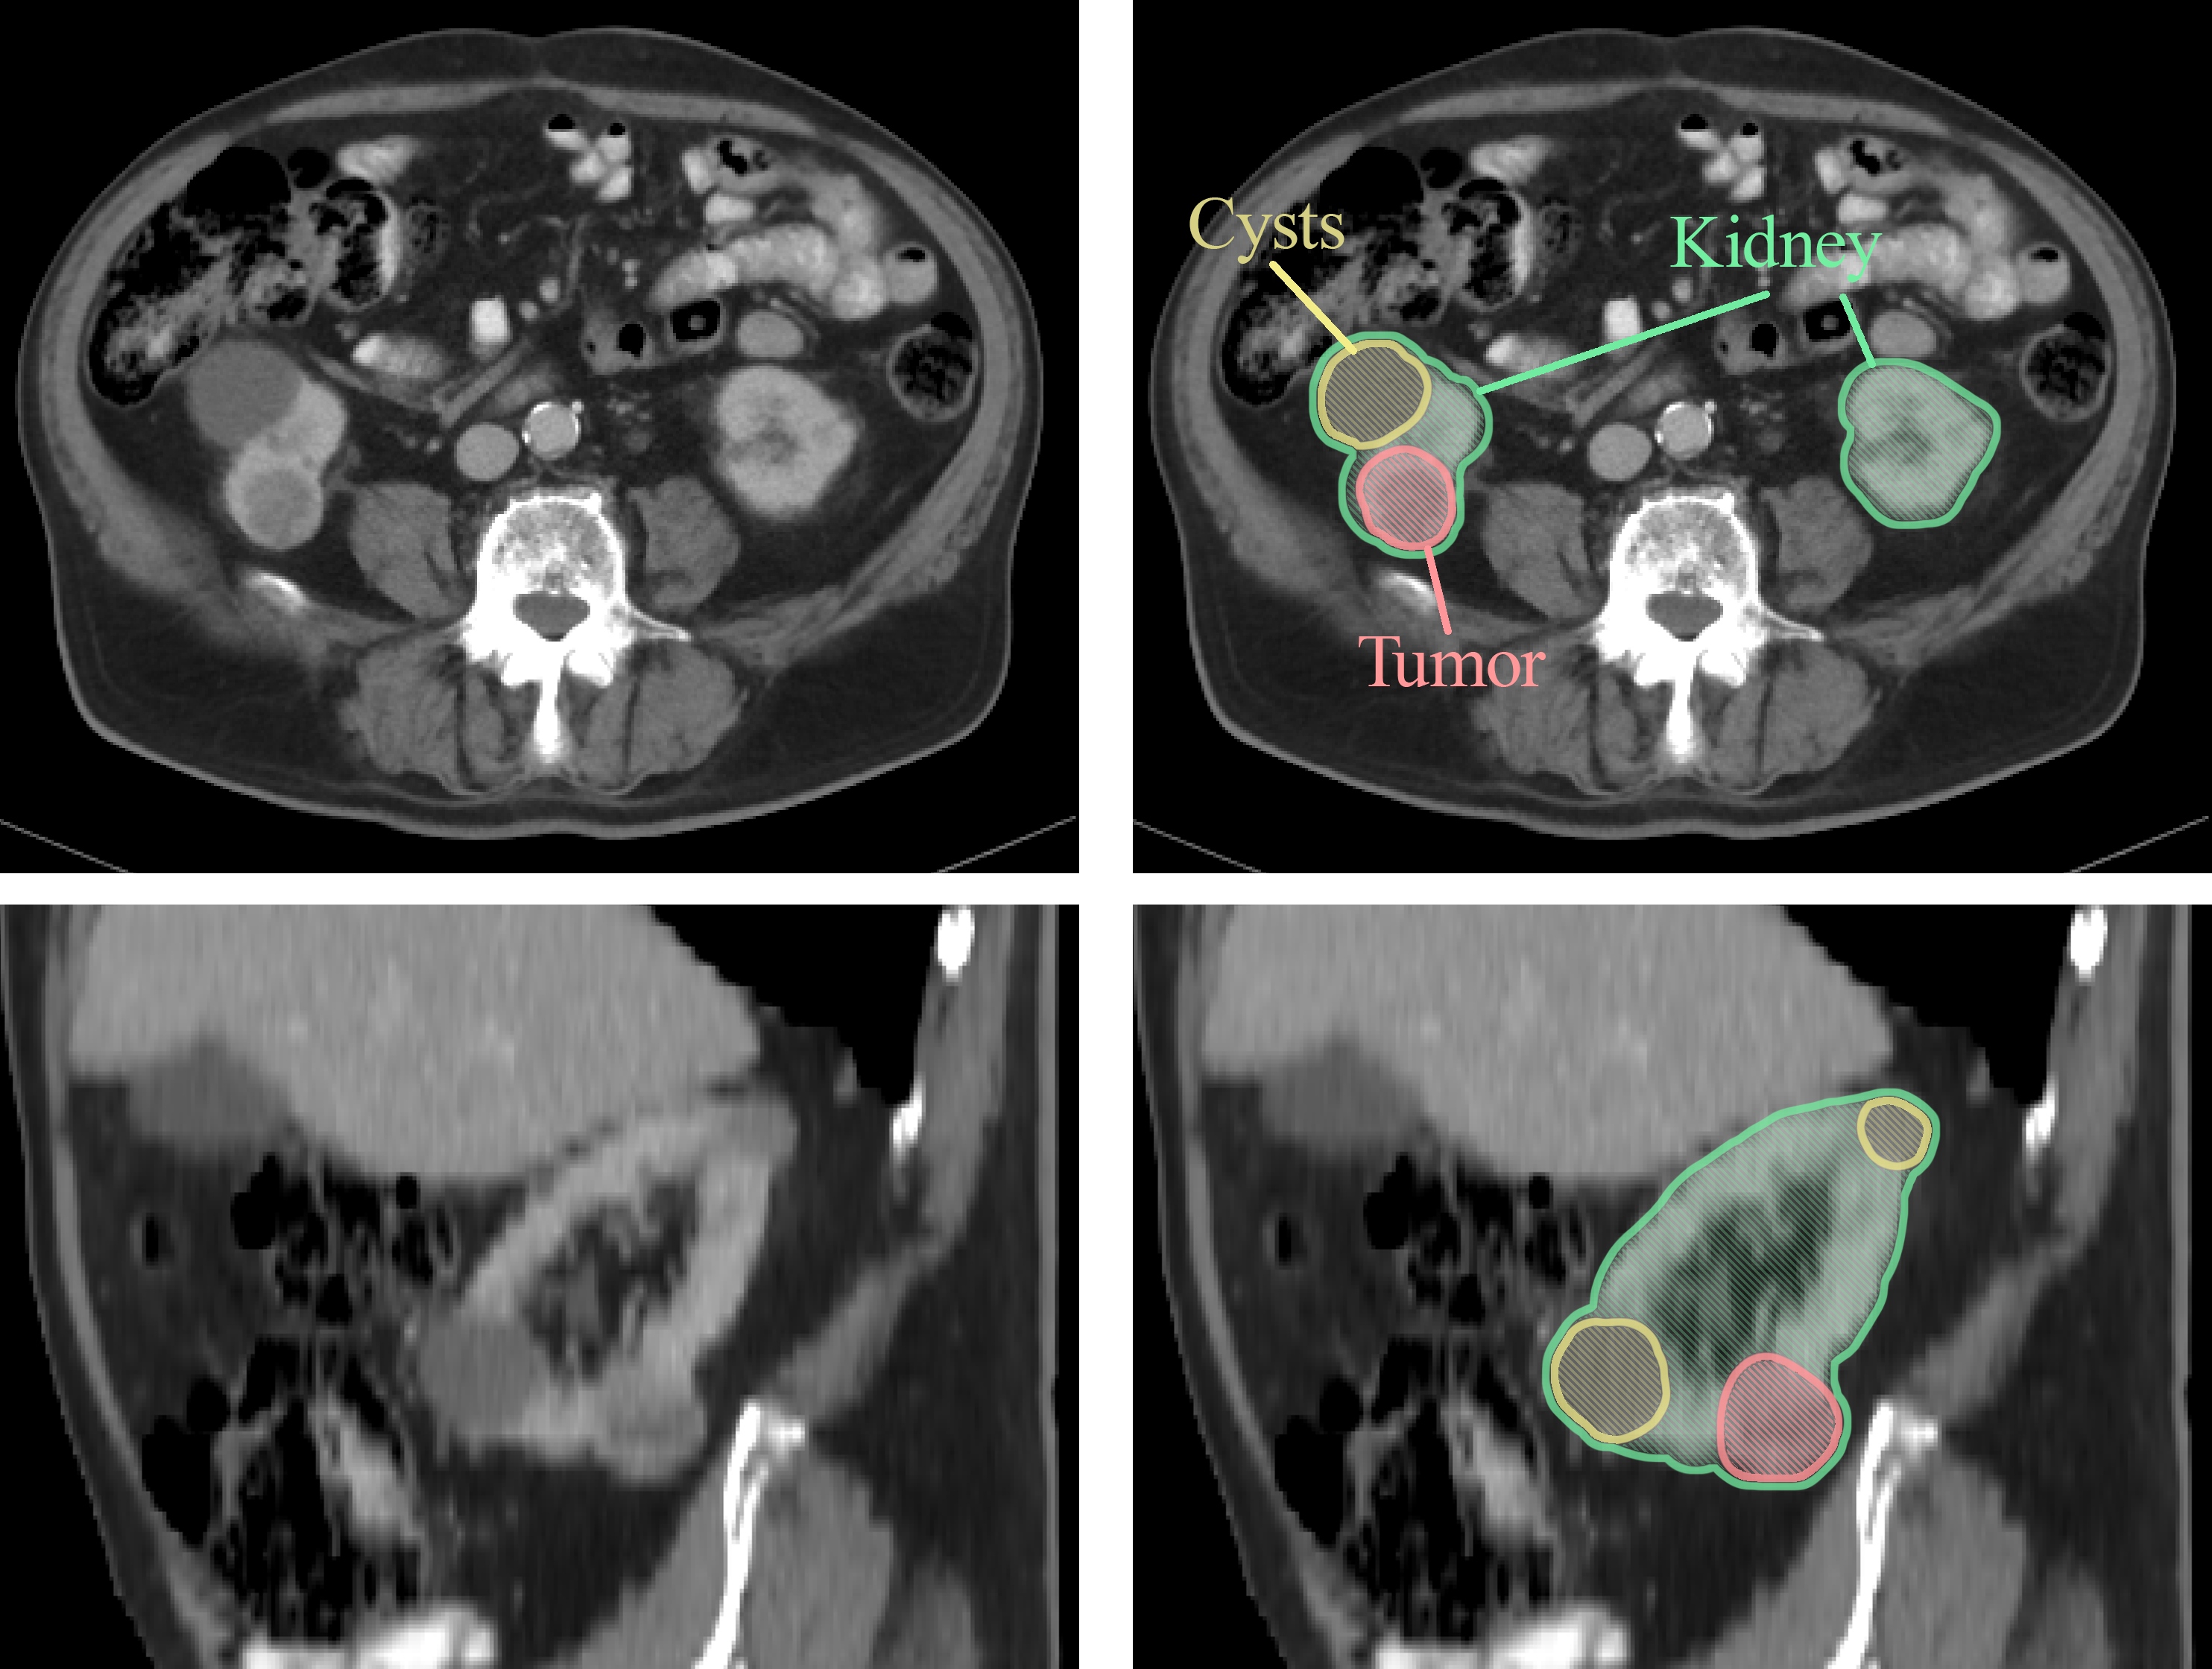

CT scan and MRI image of kidney

Currently, doctors mainly rely on imaging tests like CT scans and MRIs to diagnose kidney cancer. These scans help determine if a suspicious area is indeed cancer and whether it has spread beyond the kidney. However, even with modern imaging, it can sometimes be difficult to tell whether a kidney tumour is cancerous or benign (non-cancerous). In fact, studies show that about 10-15% of kidney masses removed during surgery turn out to be non-cancerous.